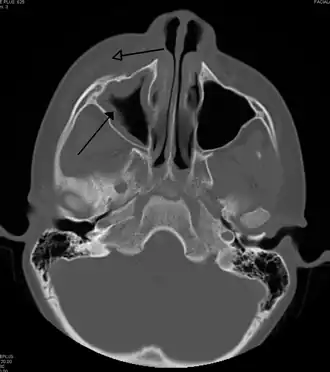

Periorbital cellulitis caused by a dental infection (also causing maxillary sinusitis)

Periorbital cellulitis, or preseptal cellulitis, is an inflammation and infection of the eyelid and portions of skin around the eye anterior to the orbital septum.[1] It may be caused by breaks in the skin around the eye, and subsequent spread to the eyelid; infection of the sinuses around the nose (sinusitis); or from spread of an infection elsewhere through the blood.

Periorbital cellulitis must be differentiated from orbital cellulitis, which is an emergency and requires intravenous (IV) antibiotics. In contrast to orbital cellulitis, patients with periorbital cellulitis do not have bulging of the eye (proptosis), limited eye movement (ophthalmoplegia), pain on eye movement, or loss of vision. If any of these features is present, one must assume that the patient has orbital cellulitis and begin treatment with IV antibiotics. CT scan may be done to delineate the extension of the infection.

Tests include blood work (CBC) to rule out infectious cause. Also perform a CT scan, x ray of the anterior skull to view the sinuses, MRI scan and finally a soft tissue ultrasound of the orbital region.